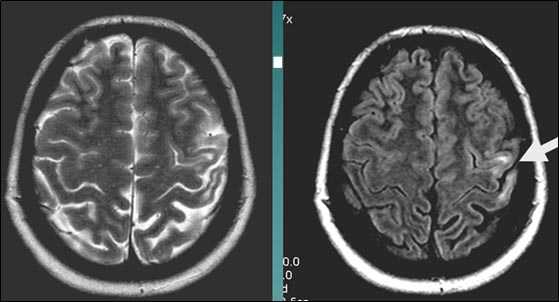

Кортикальное ишемическое НМК

Постишемическая лакунарная киста с перифокальным глиозом (средняя треть corona radiata справа)

Характерным проявлением ДЭП на МР-томограммах является наличие множественных очагов глиоза.

В белом веществе левой лобной и обеих теменных долей, преимущественно субкортикально, выявлены множественные мелкие очаги хронической ишемии (большинство локализованных в бассейне правой средней мозговой артерии).

Проявлением хронической ишемии является также развитие выраженных дистрофических изменений белого вещества паравентрикулярной локализации - лейкоареоз.

Выраженные дистрофические изменения белого вещества паравентрикулярной локализации - лейкоареоз.

Сочетание мультифокальных очаговых изменений с диффузной кортикальной церебральной атрофией.